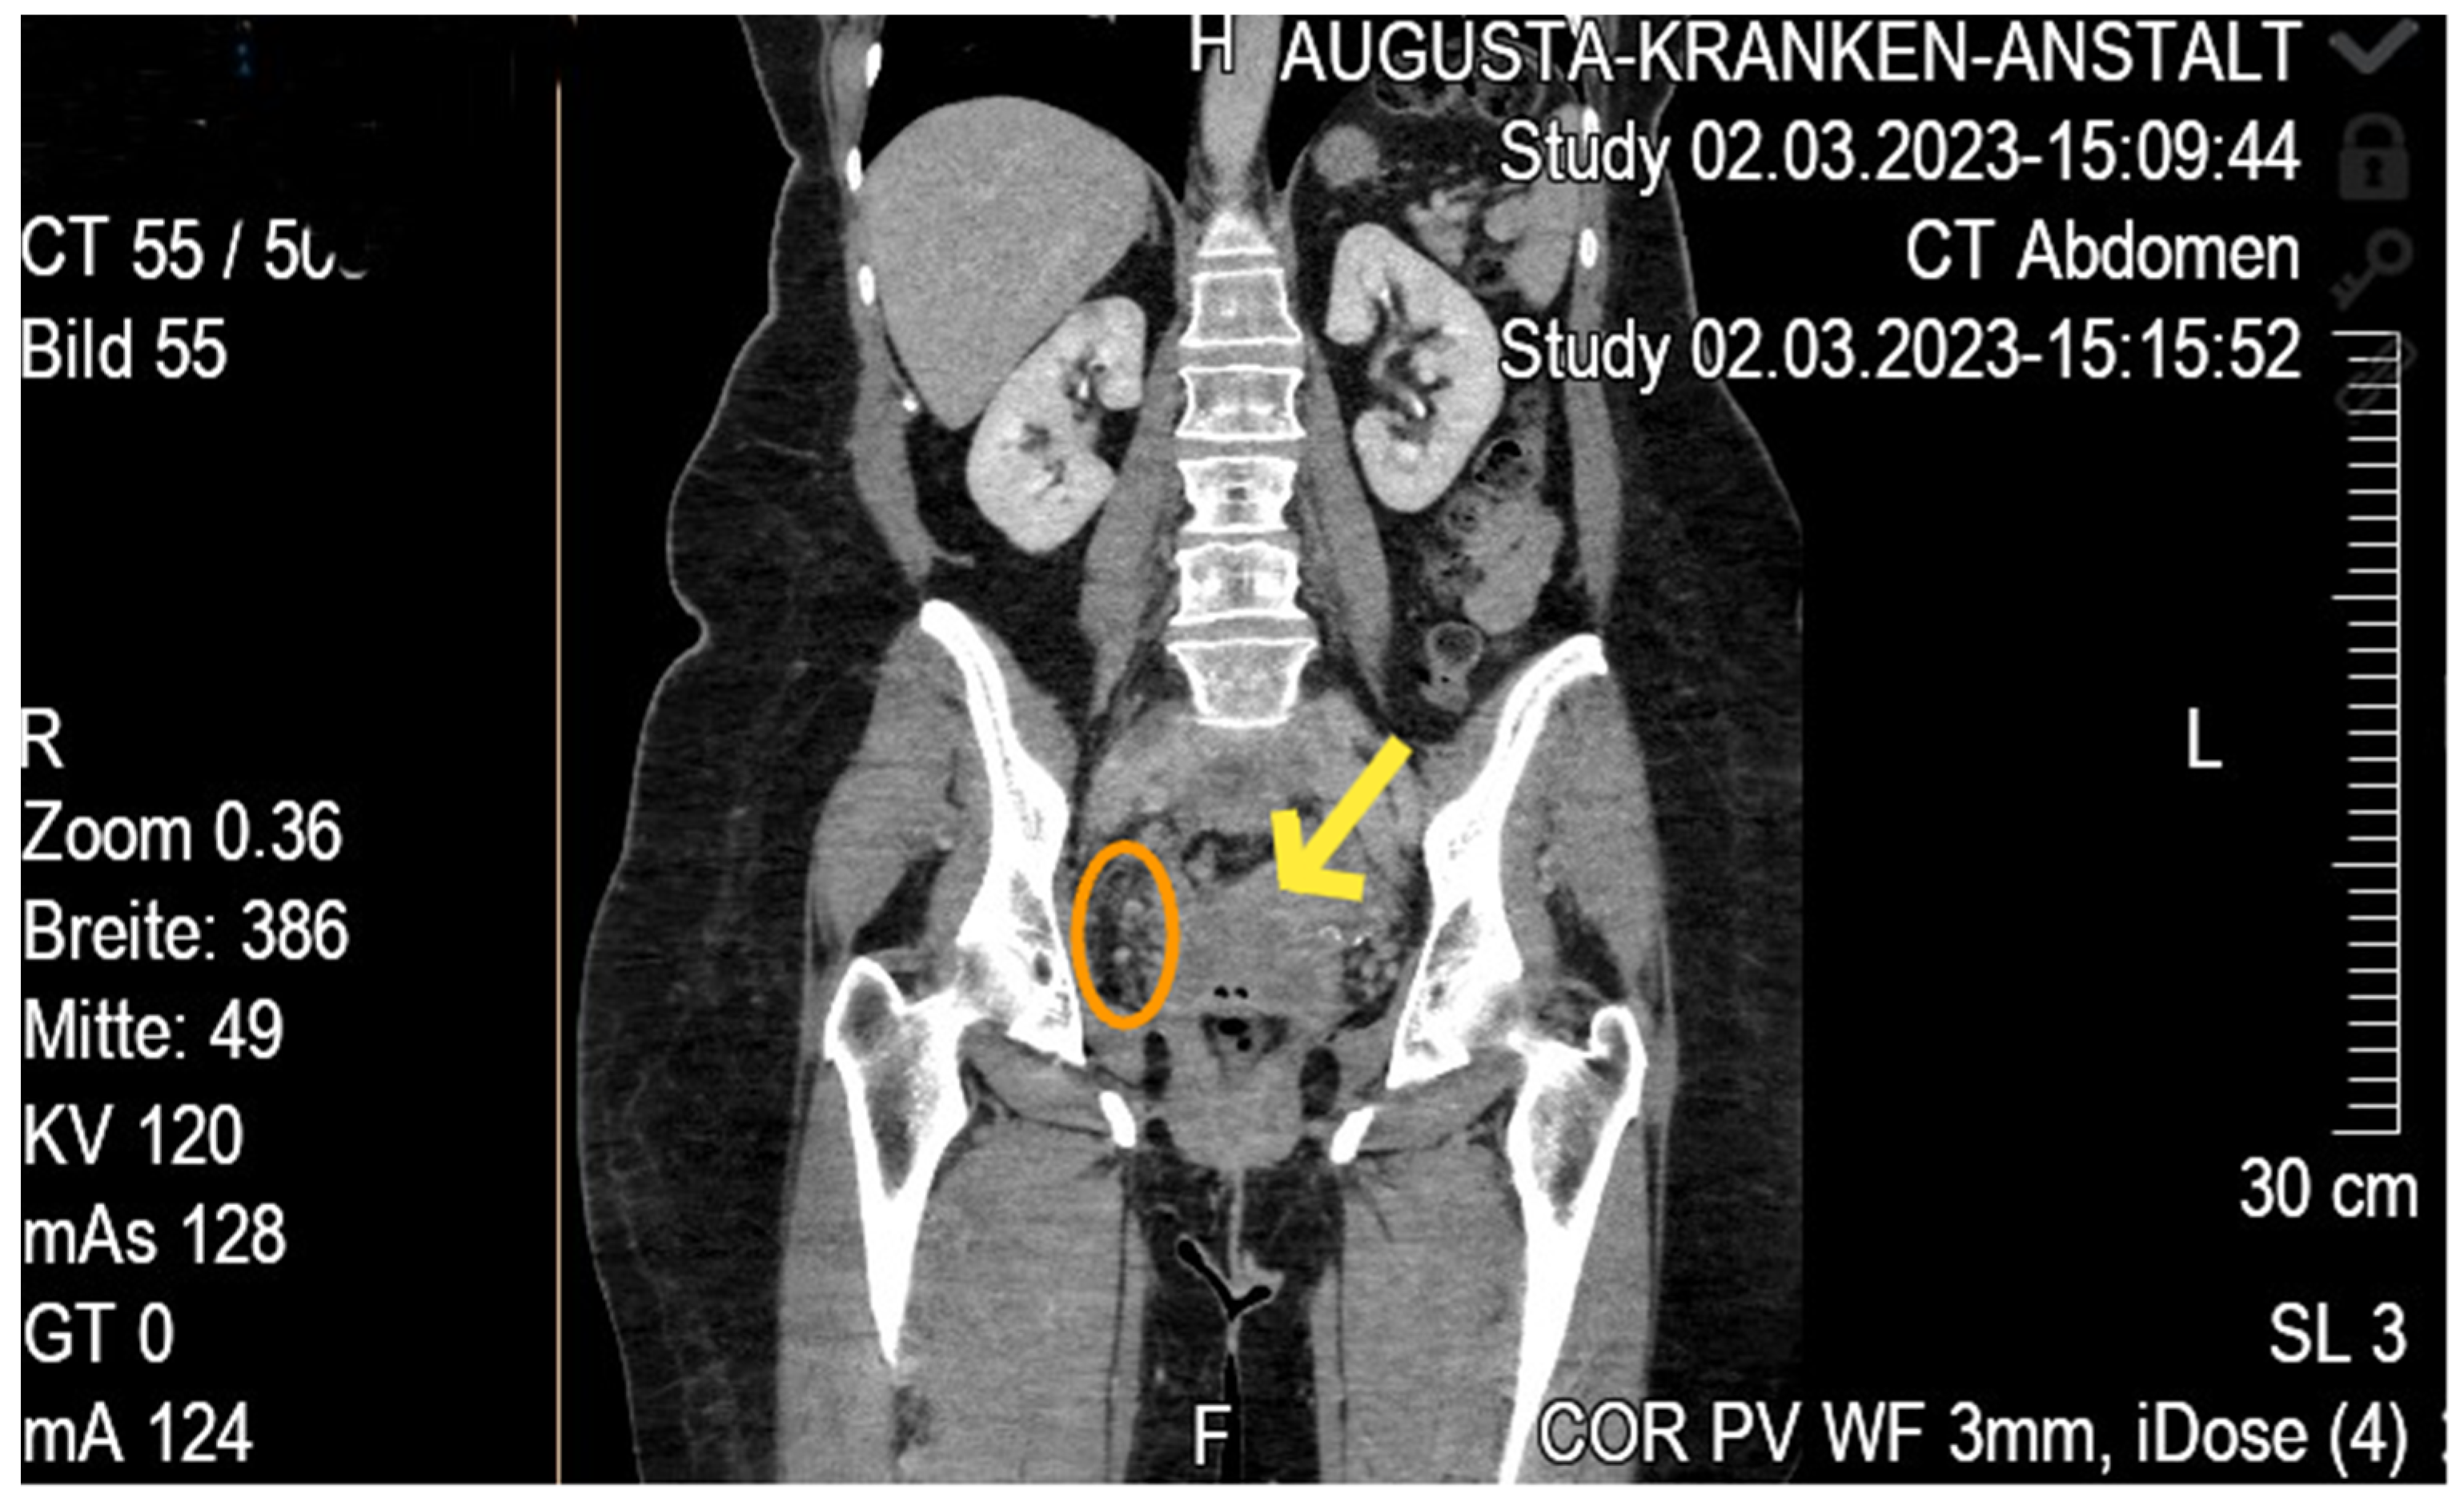

Case Report